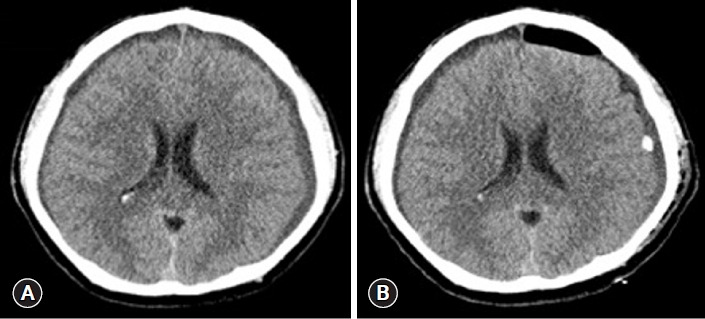

This case series highlights chronic subdural hematoma in previously healthy young and middle-aged patients, where symptoms persisted despite initial surgical intervention. Subsequent diagnosis revealed spontaneous intracranial hypotension through computed tomography myelography. All patients experienced symptom relief after undergoing epidural blood patch. In conclusion, spontaneous intracranial hypotension should be considered in chronic subdural hematoma cases without trauma or underlying disease, with epidural blood patch recommended before surgical intervention if spontaneous intracranial hypotension is suspected.

Abstract Image